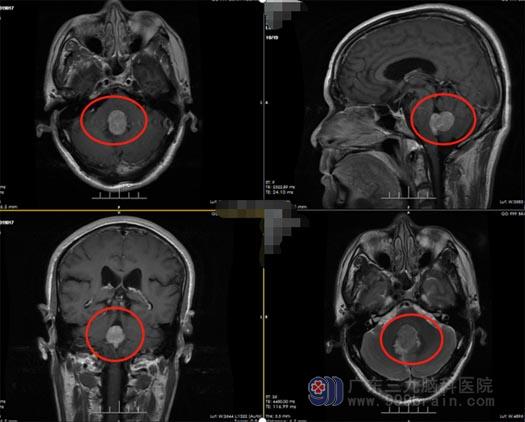

最近三个月,郭先生头痛症状不断加重,不仅头痛药没效果了,而且还出现上肢末端麻木、胃口不好等症状。为进一步治疗,家人带着他来到广东三九脑科医院外五科,完善相关的检查后,初步考虑患者四脑室占位性病变,认为是脑膜瘤可能性比较大。由于病灶处于脑室中,阻碍了脑脊液的通路,必须通过手术治疗,否则会出现脑积水甚至脑疝的危险!

肿瘤起于四脑室底部、部分与脑干粘连,郭先生的主治医生贺小军指出手术治疗的难点在于:在切除肿瘤同时,不但要保护好脑干不受损,同时也要保护好双侧小脑后下动脉,分离肿瘤,不仅要有丰富的临床经验、娴熟的技术,还要非常有耐心和耐力,稍有不慎会出现出血、梗塞等手术意外。